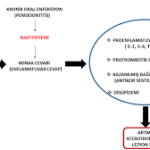

Periodontitis, diş eti ve diş çevresindeki dokuların kronik enfeksiyonu ile karakterizedir. Bu enfeksiyonlar sistemik inflamatuar yanıtı tetikleyebilir:

- Artan sistemik inflamasyon, ateroskleroz gelişimini hızlandırabilir, damar içi plak oluşumuna katkıda bulunur ve mevcut damar lezyonlarını destabilize edebilir.

- Günlük diş fırçalama, diş eti kanamaları veya periodontal cep derinliği ile bakteriler kana geçebilir.

- Bu bakteriyemi özellikle özellikle atherosklerotik plaklar üzerinde mikroorganizma yerleşimi ve inflamasyon başlatabilir.

3. Endotelyal disfonksiyon

- Periodontal enfeksiyonlar, endotelyal hücrelerde fonksiyon bozukluğu (endotelyal disfonksiyon) yaratabilir.

- Sitokinler ve lipopolisakkaritler (LPS) NO üretimini azaltır → vazodilatasyon azalır.

- Artmış inflamasyon → trombosit aktivasyonu ve vasküler inflamasyon.

- Sonuç: damar sertliği ve hipertansiyon riski artar.

4. Metabolik ve trombotik etkiler

- Periodontal hastalıklar, plazma fibrinojen, pıhtılaşma faktörleri ve trombosit agregasyonunu artırabilir.

- Bu durum trombüs oluşum riskini ve miyokard enfarktüsü gibi kardiyak olayları yükseltebilir.